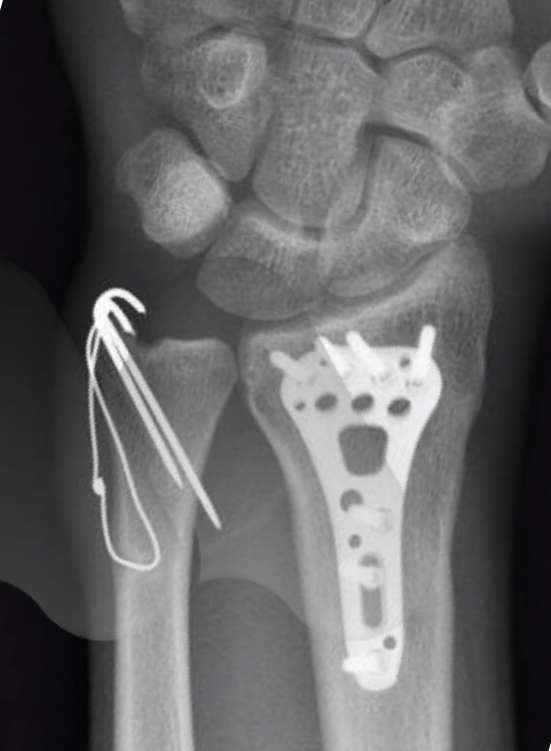

Wrist Fracture - Avanthi Mandaleson

wrist fracture ulna fixation styloid surgery